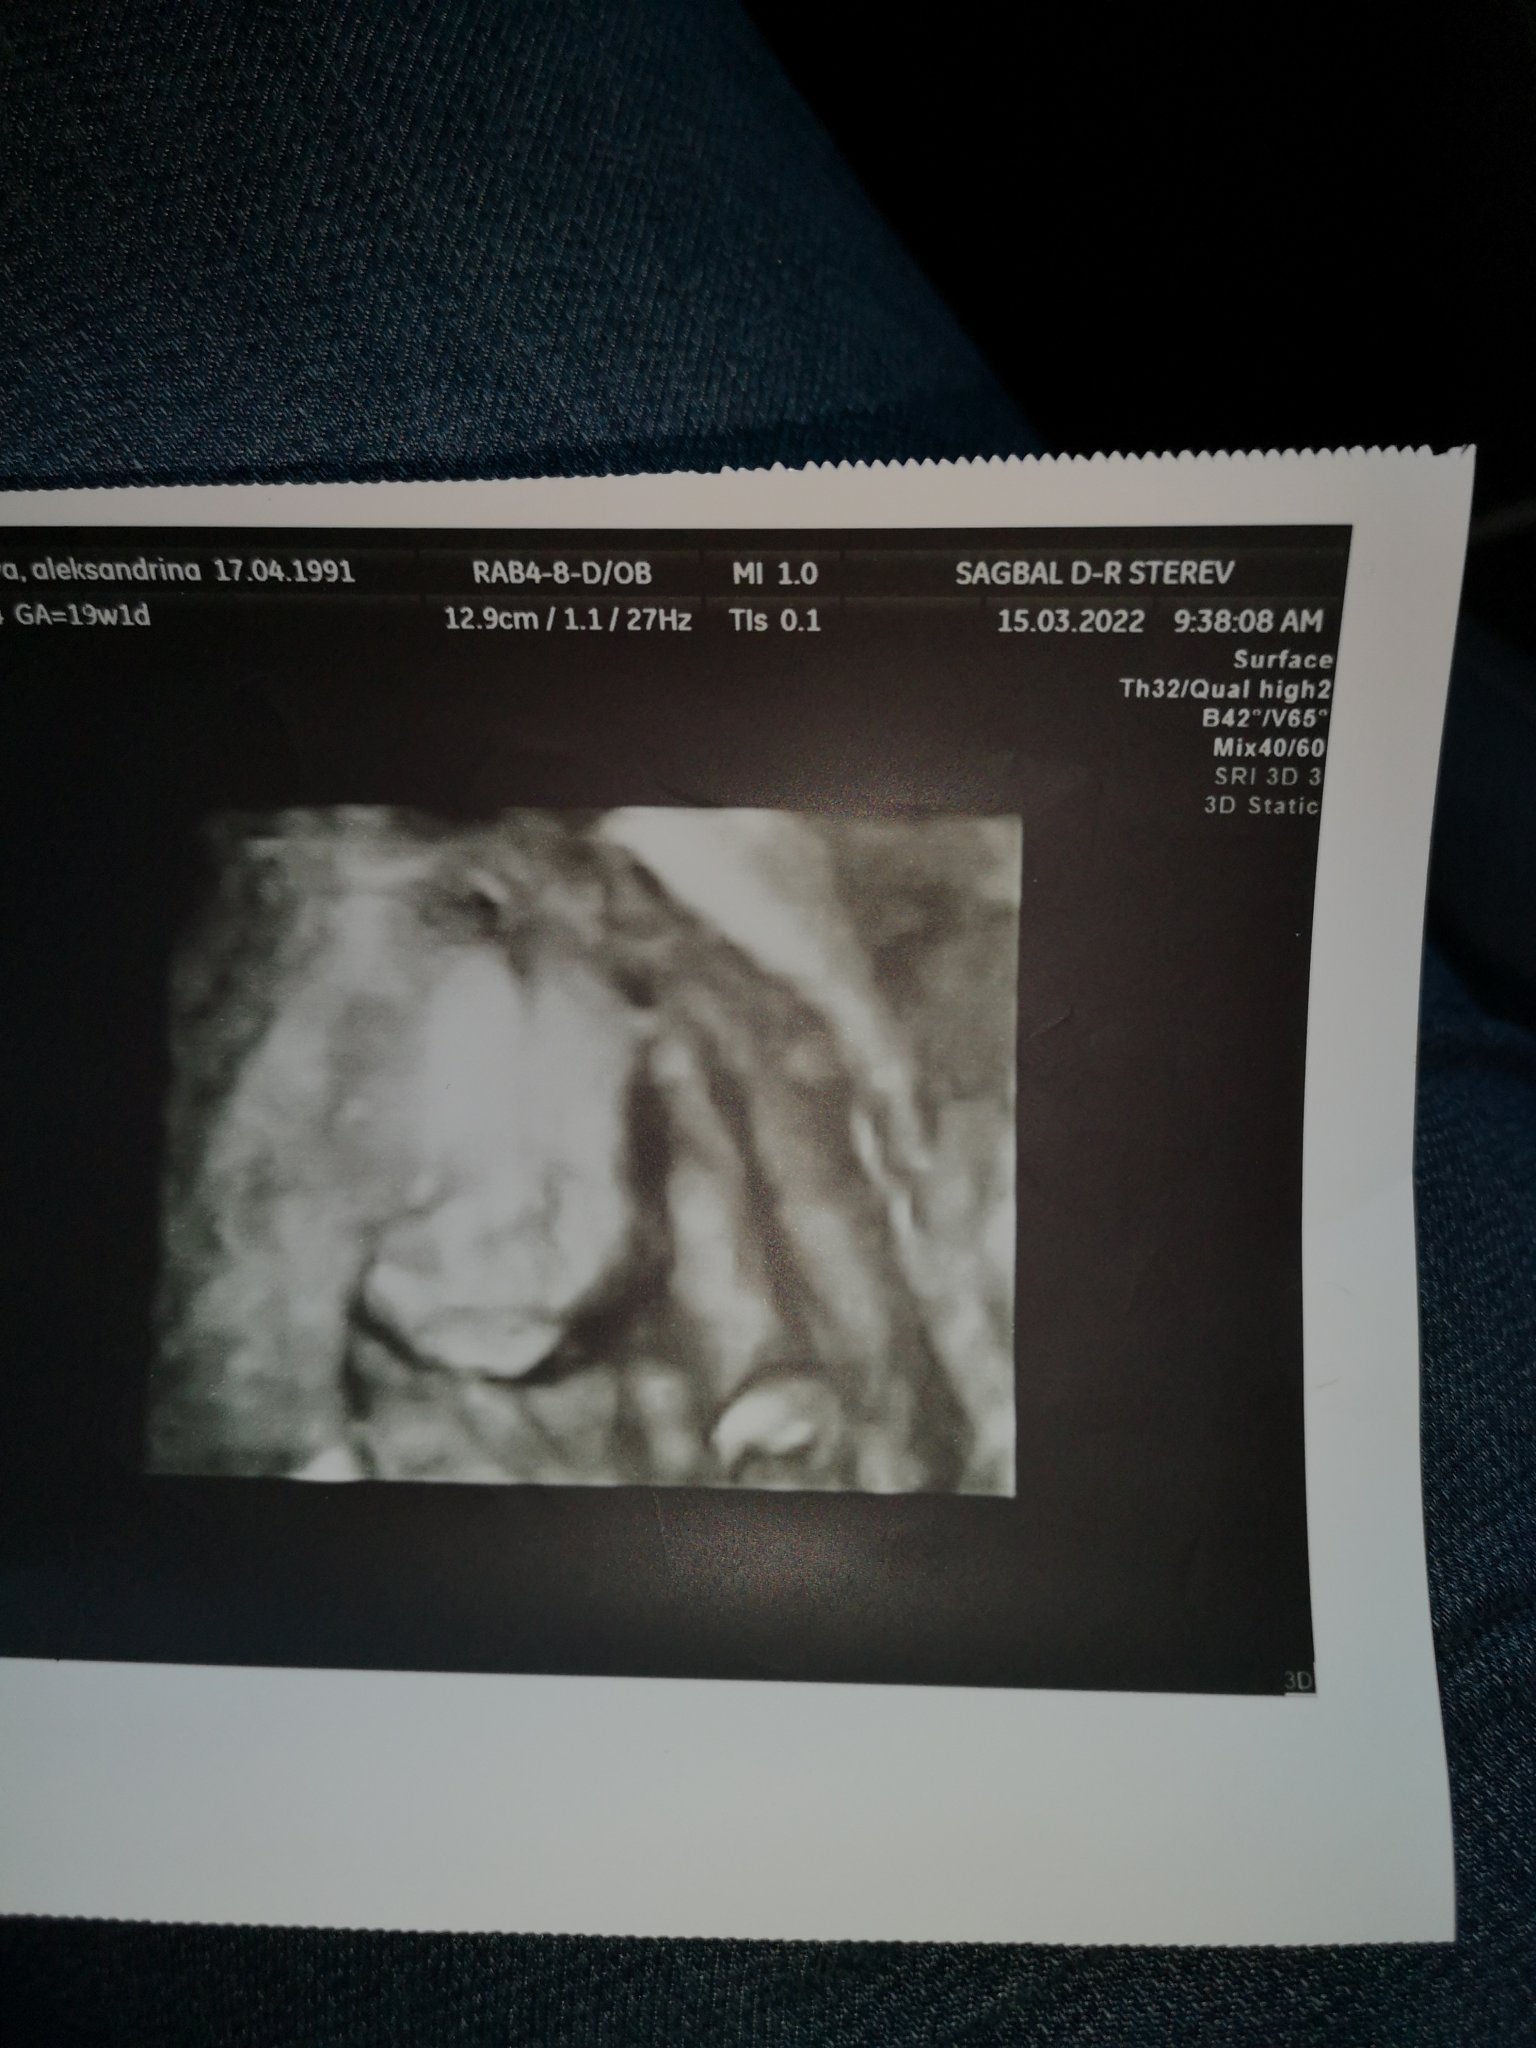

Ох момичета, тази моята малка бонбонка не ми дава миг спокойствие. Тъкмо се успокоя, че всичко е наред и днес отивам с каката на фетална, тя поне  е много доволна. Видя я- ръце, крака, личице, смучеше си пръста и хълцаше даже. НО, единия бъбрек задържа урина, подозират срастване на плацентата и матката на мястото  на старото секцио. Искат да ме гледат пак след 2 седмици, като прегледа ще е отново тип фетална, после ще изпия завидно количество вода, за да се издуе пикочния мехур и да се опъне стената на матката със среза и ще ме гледат с вафиналвн ехограф.

Показвам ви я и на вас. Стиснете по един палец.